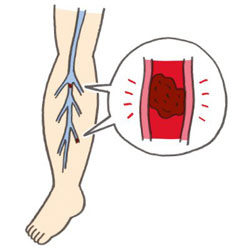

深部静脈血栓症イラスト - No: 24599005無料イラスト・フリー素材なら「イラストAC」。

深部静脈血栓症イラスト無料イラスト・フリー素材なら「イラストAC」。

上皇后さまが発症された深部静脈血栓症について解説します下肢静脈瘤の原因・症状・治療方法・予防方法などを専門医が解説。

脚領域における深部静脈血栓症の医学的図。のイラスト素材・ベクター Image 98030310。

深部静脈血栓症 DVT の病態と予防見て!わかる!病態生理と看護 花子のまとめノート。

深部静脈血栓症 - 血栓のベクターアート素材や画像を多数ご用意 - 血栓, 肺塞栓症, イラストレーション - iStock。

深部静脈血栓症、血栓症。塞栓。正常静脈と静脈瘤の構造。イラストは私が作成しました写真素材1443942500Shutterstock。

深部静脈血栓症イラスト無料イラスト・フリー素材なら「イラストAC」。